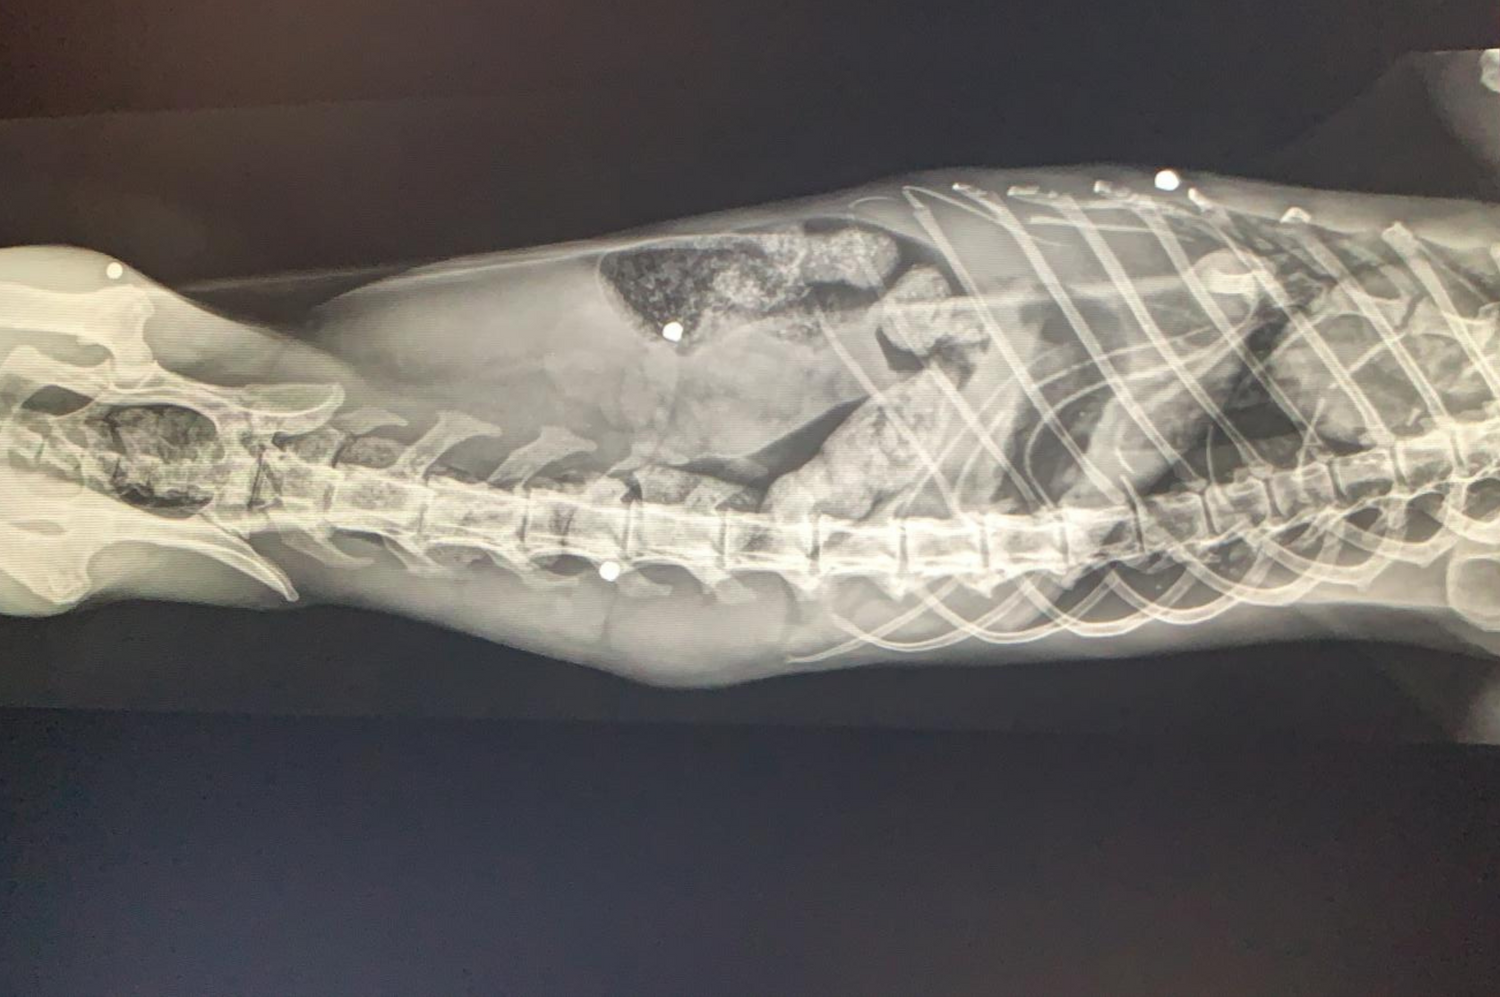

Der 15-jährige, blinde Kater "Tizian" wurde offenbar mit einem Schrotgewehr angeschossen.